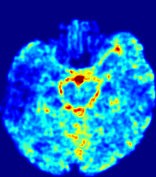

LesionRefer to captionRefer to captionRefer to captionRefer to captionRefer to captionRefer to caption𝐕rgbsubscript𝐕𝑟𝑔𝑏{\bf{V}}_{rgb}Refer to captionRefer to captionRefer to captionRefer to captionRefer to captionRefer to caption𝐕2subscriptnorm𝐕2{\|\bf{V}}\|_{2}Refer to captionRefer to captionRefer to captionRefer to captionRefer to captionRefer to captionRefer to caption3.53.53.52.82.82.82.12.12.11.41.41.40.70.70.70.00.00.0(mm/s)𝑚𝑚𝑠(mm/s)D𝐷DRefer to captionRefer to captionRefer to captionRefer to captionRefer to captionRefer to captionRefer to caption0.0200.0200.0200.0160.0160.0160.0120.0120.0120.0080.0080.0080.0040.0040.0040.0000.0000.000(mm2/s)𝑚superscript𝑚2𝑠(mm^{2}/s)Slice #1Slice #2Slice #3Slice #4Slice #5Slice #6

Figure 4: PIANO feature maps for another patient in the ISLES 2017 training set, where the lesion is located in the right hemisphere. Top row: segmented stroke lesion region (white) on different slices. The corresponding slices for the PIANO feature maps are shown in the following rows.

For a better insight into an estimated velocity field 𝐕𝐕{\bf{V}} and diffusion field 𝐃𝐃{\bf{D}}, we compute the following maps: (1) 𝐕rgbsubscript𝐕𝑟𝑔𝑏{\bf{V}}_{rgb}: Color-coded orientation map of 𝐕=(Vx,Vy,Vz)T𝐕superscriptsuperscript𝑉𝑥superscript𝑉𝑦superscript𝑉𝑧𝑇{\bf{V}}=(V^{x},V^{y},V^{z})^{T}, obtained by normalizing 𝐕𝐕{\bf{V}} to unit length and mapping its 3 components to red, green, blue respectively; (2) 𝐕2subscriptnorm𝐕2\|{\bf{V}}\|_{2}: 222 norm of 𝐕𝐕{\bf{V}}; (3) D𝐷D: scalar field in Eq. 5.

Fig. 3 and Fig. 4 show the PIANO feature maps estimated from two ISLES 2017 patients: all are highly consistent with the lesion in both cases. Details of the blood flow trajectories are revealed in 𝐕rgbsubscript𝐕𝑟𝑔𝑏{\bf{V}}_{rgb} by the ridged patterns and the sharp changes of colors in the unaffected (right) hemisphere, while the flat patterns appearing within the lesion provide little directional information about the velocity and indicate low velocity magnitudes. Velocity magnitudes are more directly visualized via 𝐕2subscriptnorm𝐕2\|{\bf{V}}\|_{2}, from which one can easily locate the lesion where 𝐕2subscriptnorm𝐕2\|{\bf{V}}\|_{2} is low. D𝐷D also indicates lower diffusion values in the lesion, though with less contrast potentially due to the fact that it captures the accumulated effect of CA diffusion at the voxel-level.